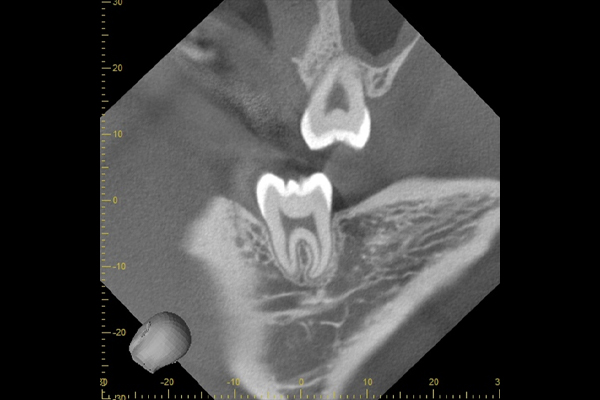

上顎親知らずのCT画像です。直上の黒い部分が上顎洞になります。根の先が上顎洞に一部入っているように見えます。こういう場合は上顎洞粘膜の穿孔がおこりやすいといえますが、この症例では穿孔せずにすみました。

下顎の親知らずのCT画像です。根の先に黒い円があります。これが顎の骨の中にある神経になります。この症例では、近いですが、接してはいないため、神経をきずつけるリスクは少ないといえます。